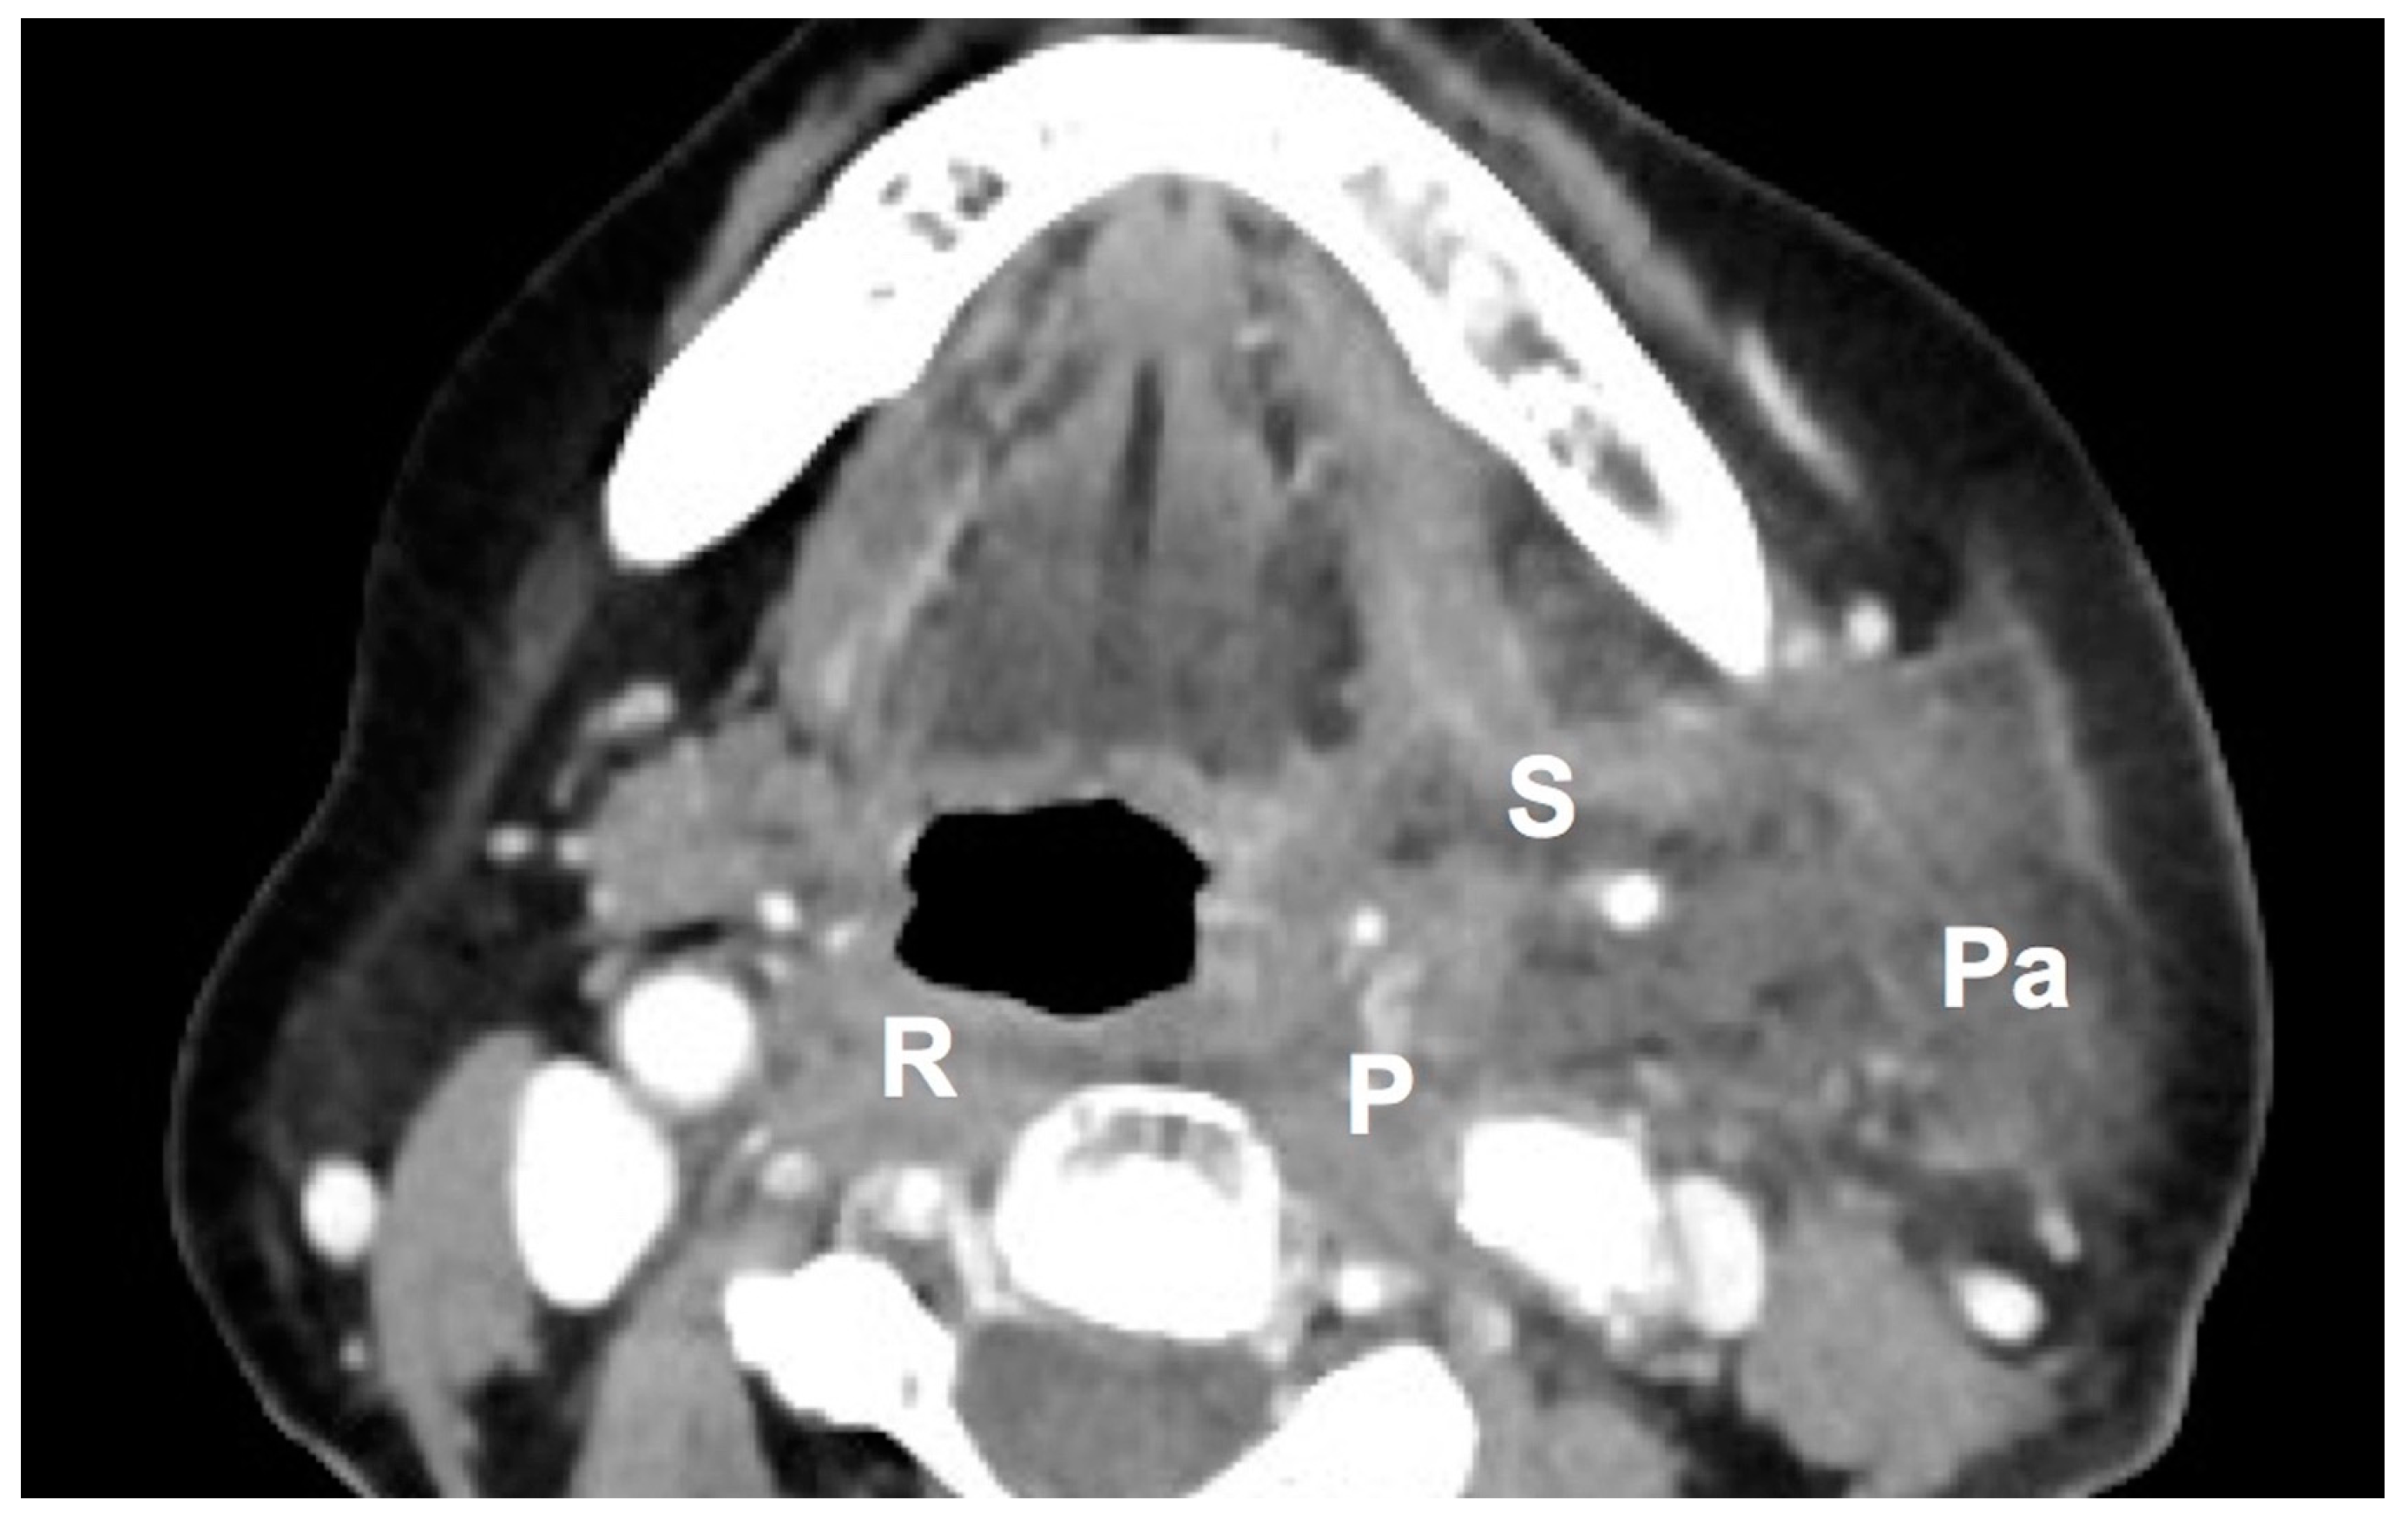

| Parapharyngeal space | 32 (72.72) | 210 (58.49) | 0.074 |

| Retropharyngeal space | 22 (50.00) | 132 (36.76) | 0.100 |

| Submandibular space | 20 (45.45) | 165 (45.96) | 1.000 |

| Masticator space | 14 (31.81) | 75 (20.89) | 0.122 |

| Anterior cervical space | 9 (20.45) | 45 (12.53) | 0.159 |

| Parotid space | 5 (11.36) | 77 (21.44) | 0.163 |

| Perivertebral space | 5 (11.36) | 19 (5.29) | 0.164 |

| Carotid space | 4 (9.09) | 19 (5.29) | 0.298 |

| Visceral space | 3 (6.81) | 21 (5.84) | 0.736 |

| Posterior cervical space | 1 (2.27) | 7 (1.94) | 1.000 |